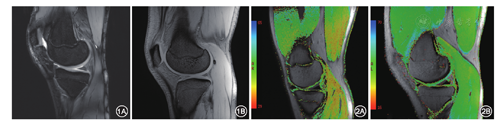

采用德国Siemens 3.0 T Skyra高场强MR扫描仪,15通道膝关节表面线圈。扫描序列包括高分辨率冠状位、矢状位质子脂肪抑制序列(fat saturation protein density weighted imaging,FS-PDWI)、矢状位T2图(T2-mapping)(图1,图2,图3)。

矢状位FS-PDWI:重复时间(TR)3 000 ms,回波时间(TE)25 ms,视野(FOV)170 mm×170 mm,矩阵320×320,层厚3.0 mm,扫描时间4 min 30 s;冠状位FS-PDWI:TR 3 570 ms,TE 43 ms,FOV 170 mm×170 mm,矩阵320×320,层厚3.0 mm,扫描时间5 min 21 s。T2-mapping:TR 1 000 ms,TE1=13.8、TE2=27.6、TE3=41.4、TE4=55.2、TE5=69.6 ms,FOV 160 mm×160 mm,矩阵384×384,层厚3.0 mm,扫描时间6 min 54 s。